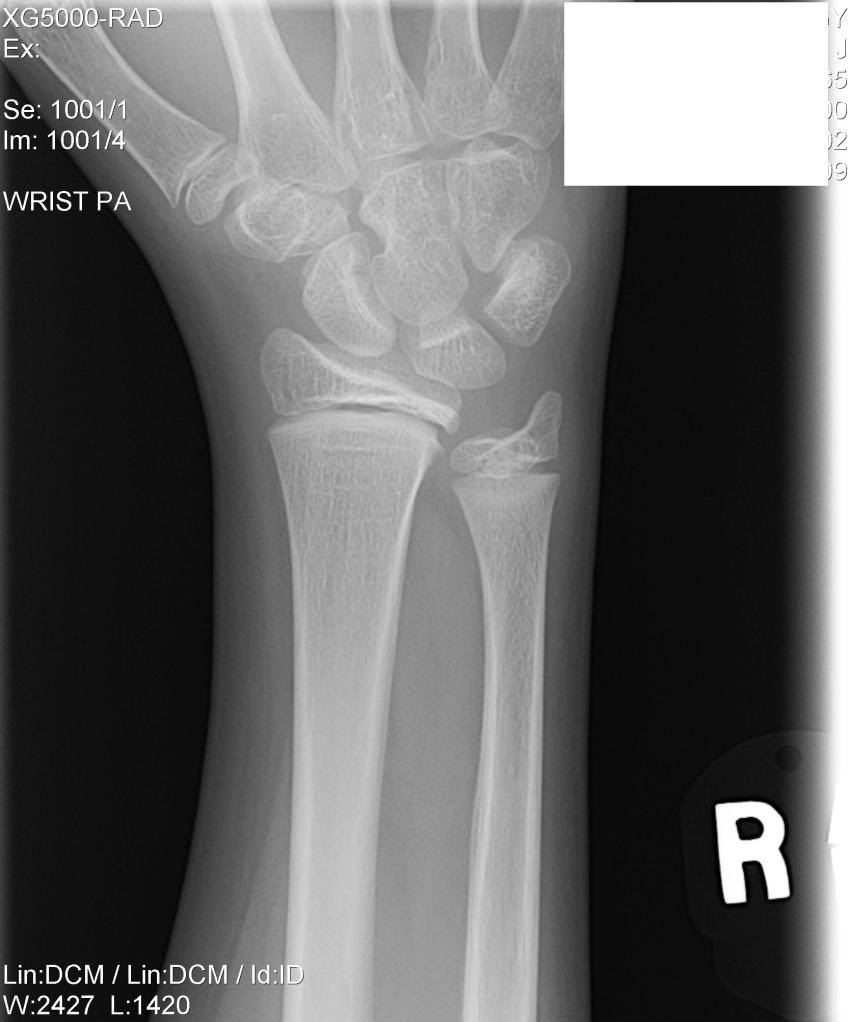

Ulna Hairline Fracture How Long Does A Broken Wrist With A Plate Take To Heal How long does it take a broken wrist to heal? You might need surgery to help your wrist heal, and severe breaks can take up to 6 months of recovery time. However, some complex fractures may require surgery to heal properly. A broken wrist causes immediate pain, swelling, tenderness, and bruising. It will take about six weeks for your bone. How Long Does A Broken Wrist With A Plate Take To Heal.

Different Types Of Wrist Fractures The Bone Joint Cen vrogue.co How Long Does A Broken Wrist With A Plate Take To Heal If your wrist is broken in. You won't be able to lift or push things until it heals, which takes about 6 to 12 weeks. You might need surgery to implant pins, plates, rods or screws to hold your bones in place while they heal. A broken wrist causes immediate pain, swelling, tenderness, and bruising. You might need surgery to. How Long Does A Broken Wrist With A Plate Take To Heal.